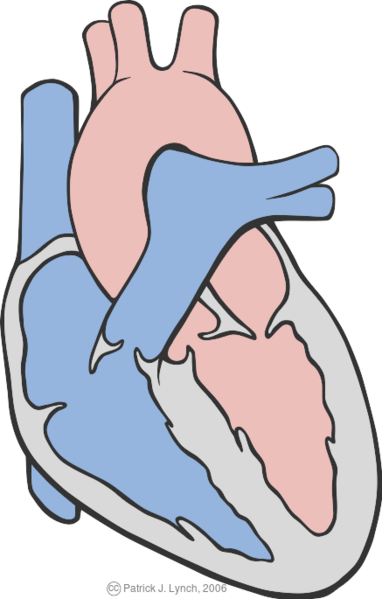

The normal conduction system of the heart |

Patrick Lynch, medical illustrator |

Patrick Lynch, medical illustrator |

Creative Commons Attribution-Noncommercial-Share alike 3.0 License 2007 |